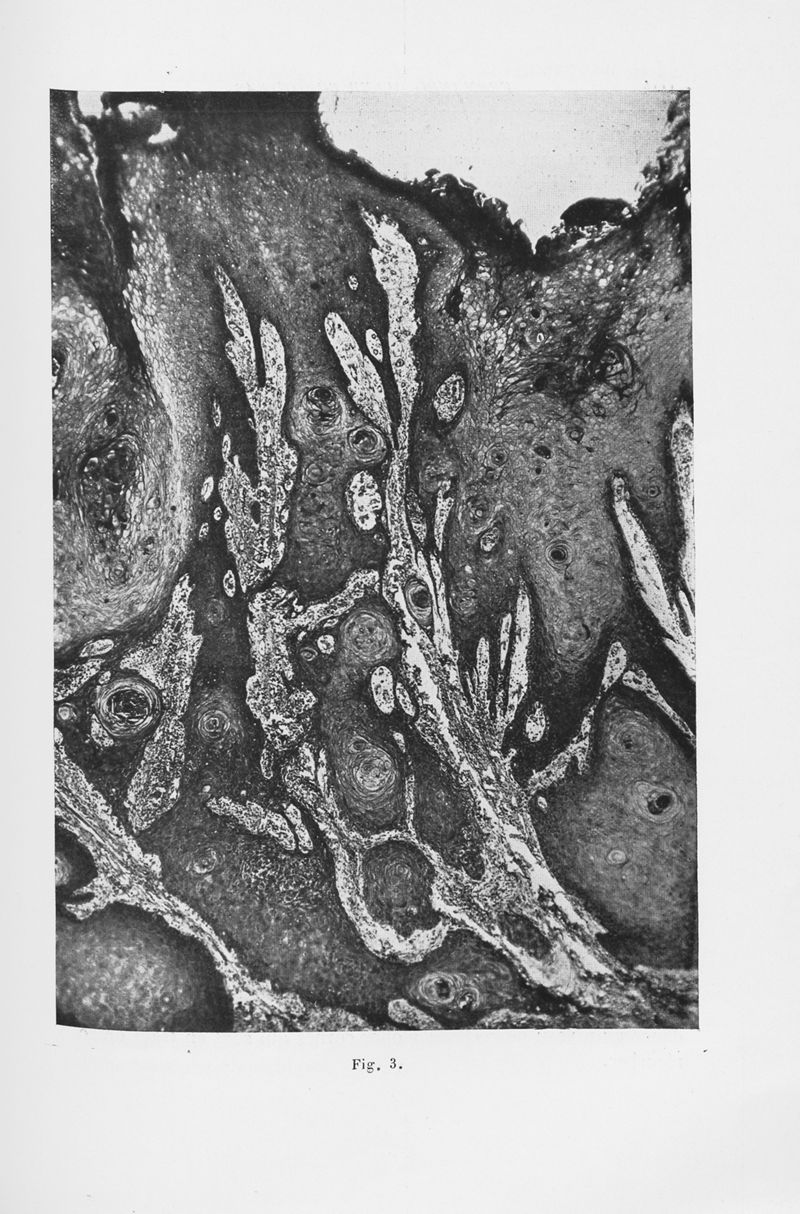

Annales de dermatologie et de syphiligraphie

7ème série, tome VI. - Paris : Masson, 1935.